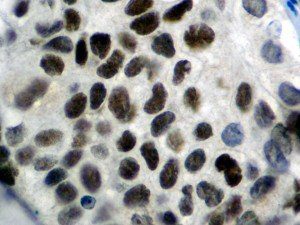

The first cytokines released are interleukin 1β (IL-1β) and tumor necrosis factor-α (TNF-α), which attract a variety of circulating white blood cells (WBCs) to the infection site, including neutrophils, monocytes, macrophages, and natural killer (NK) cells. This response, along with the antipathogenic chemicals released by these cells (i.e., complement), comprise the innate immune response. These cells directly attack the invading pathogen and also release additional cytokines, chief among them interleukin-1 and 6 (IL-6). IL-6 is essential for invoking the adaptive immune response, which calls T-cells, B-cells, and T helper (Th) cells to the infection site. IL-6 also stimulates further recruitment, proliferation and activation of macrophages.

It is the ICU physician who is most likely to witness one of the deadliest manifestations of the abnormal immunological response, the cytokine storm syndrome (CSS). This response is also referred to by some as the cytokine release syndrome (CRS). CSS is characterized by continuous activation and expansion of macrophage and lymphocyte populations, which secrete large amounts of cytokines, causing the cytokine storm. This massive cytokine release is akin to hemophagocytic lymphohistiocytosis (HLH) disease, a syndrome characterized by initial unchecked and persistent activation of cytotoxic T lymphocytes and NK cells.

Clinical and laboratory manifestations of HLH include fever, enlarged liver and/or spleen, neurologic dysfunction, coagulopathy, liver dysfunction, cytopenias (i.e., low levels of erythrocytes, leukocytes, and/or platelets), hypertriglyceridemia, hyperferritinemia, hemophagocytosis, and eventually diminished NK cell activity as the immune system becomes progressively paralyzed. HLH can be familial (primary HLH) or secondary to another disease process (sHLH), such as rheumatic disease, in which it is referred to as macrophage activation syndrome (MAS, characterized by elevated ferritin).